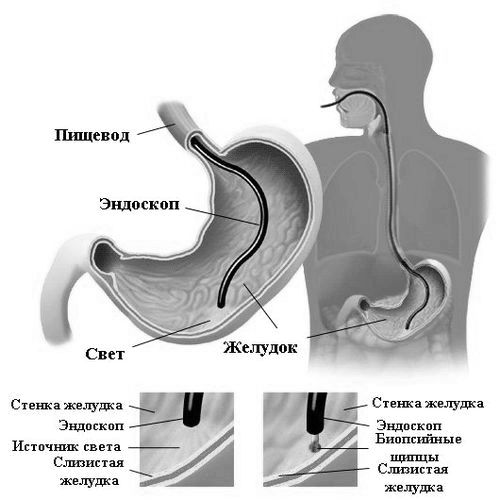

Для діагностики гастриту проводять ультразвукове дослідження, потім обстежують верхню частину травного тракту і призначають аналізи. Аналізи проводять для дослідження складу крові, сечі і калу. Може бути показана біопсія тканин стінок шлунка. Після оцінки результатів аналізів доктор визначить ступінь кислотності шлункового соку і призначить відповідне лікування.